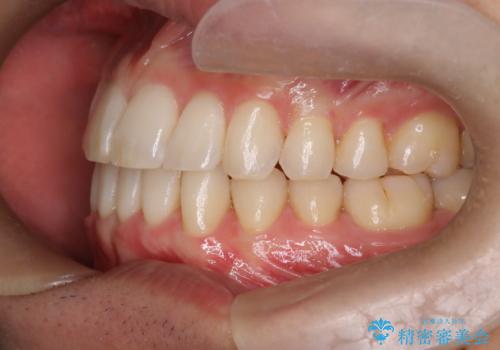

前歯の重なりとガタガタをマウスピースで改善した症例

初診時の歯並びの状態としては、上下ともに前歯部の中等度のがたつきがあり、上の前歯が重なっている状態でした。

抜歯は必要なく、マウスピース矯正にて治療を行っています。

見た目、嚙み合わせ及び、治療期間や施術内容に大変ご満足いただきました。